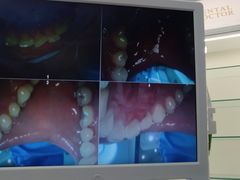

• 牙博士口腔品牌连锁(杨浦店)

• -牙博士口腔品牌连锁(杨浦店)

日料与海鲜共舞 | 21-03-03